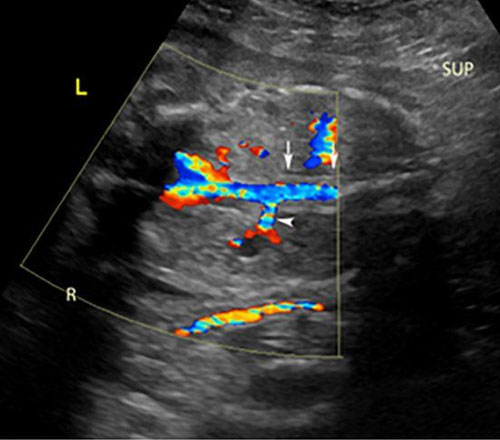

Figure 3: Coronal view showing left sided renal agenesis with a “lying down” left adrenal sign (vertical arrow), right renal artery on color Doppler to document presence of the right kidney (horizontal arrow) [38]. Radiological images were obtained from open-access article distributed under the terms of the Creative Commons Attribution License (CC BY) [38].

Kidneys can be visualized on ultrasound as early as 12 weeks gestation. However, unilateral or bilateral renal agenesis is most often discovered during an anatomy ultrasound examination at 18–22 weeks gestation. Key imaging findings include an empty renal fossa with the absence of kidneys in axial, sagittal, and coronal planes at the spine level and below the stomach. The “lying-down” adrenal sign, which is a large and flat appearance of the adrenal glands, an absence of the renal artery at a 90° angle in the coronal plane, and an absence of the fetal bladder are all key diagnostic features that may be visualized (Figure 3). Assessment for a pelvic or ectopic kidney should be performed if unilateral renal agenesis is suspected. Bilateral renal agenesis (RA) is suspected when the bladder cannot be visualized in the setting of anhydramnios.

If diagnosis of unilateral RA was made in the 2nd trimester, perform a 3rd trimester ultrasound follow-up. If bilateral RA is suspected, consider a magnetic resonance imaging (MRI) to get a specific diagnosis, identifying the underlying cause of oligohydramnios to appropriately counsel parents along with palliative care and pediatric urology (Figure 3).